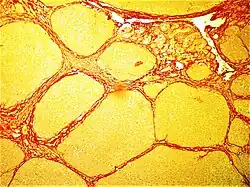

- Lipedema (fat cells, typically in lower limbs)